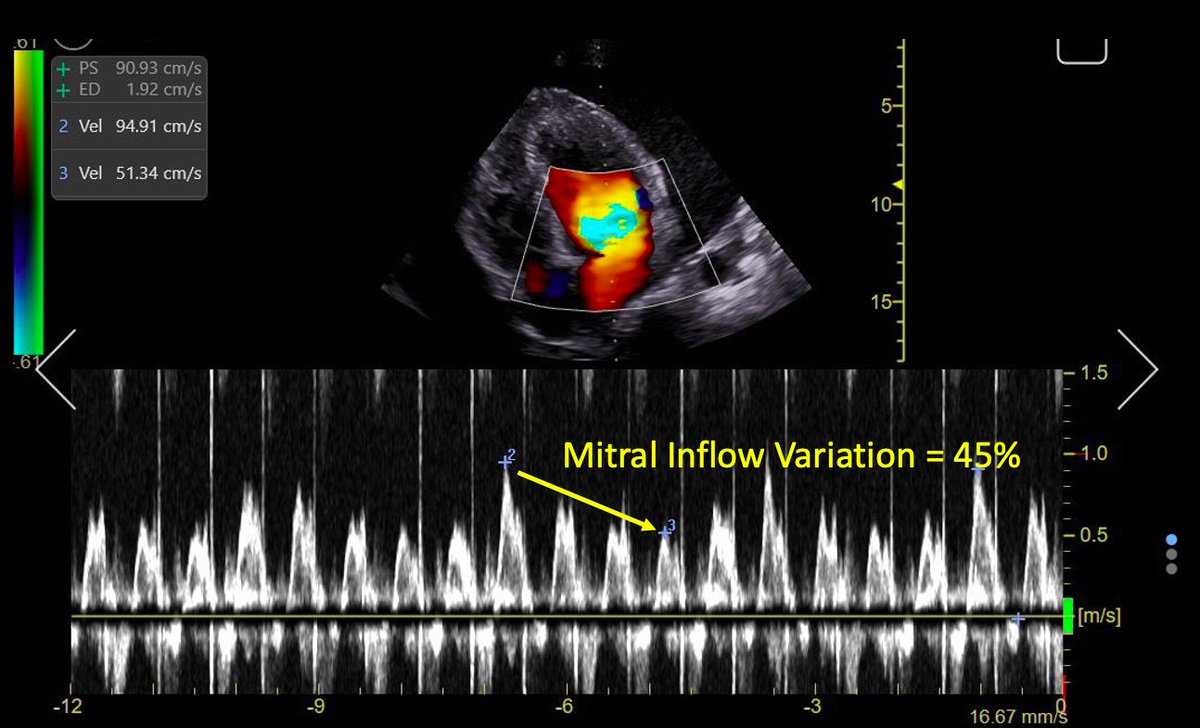

Another sign of tamponade is the equivalent of "pulsus paradoxus":

During inspiration, ⬆️ ventricular interdependence cases ⬇️ flow. So changes in flow with respiration are expected in tamponade

Trans-Mitral, Trans-Tricuspid and LVOT VTI: Significant variation!

10/13

Tamponade Physiology is present!